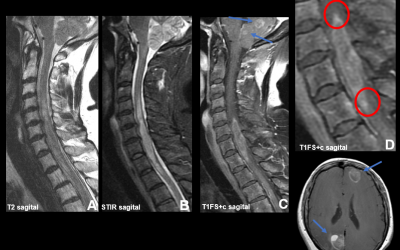

Caso del mes Marzo 2026

« Todos los casosAutores Clara de Arriba Heras, Hospital Universitario 12 de Octubre,...